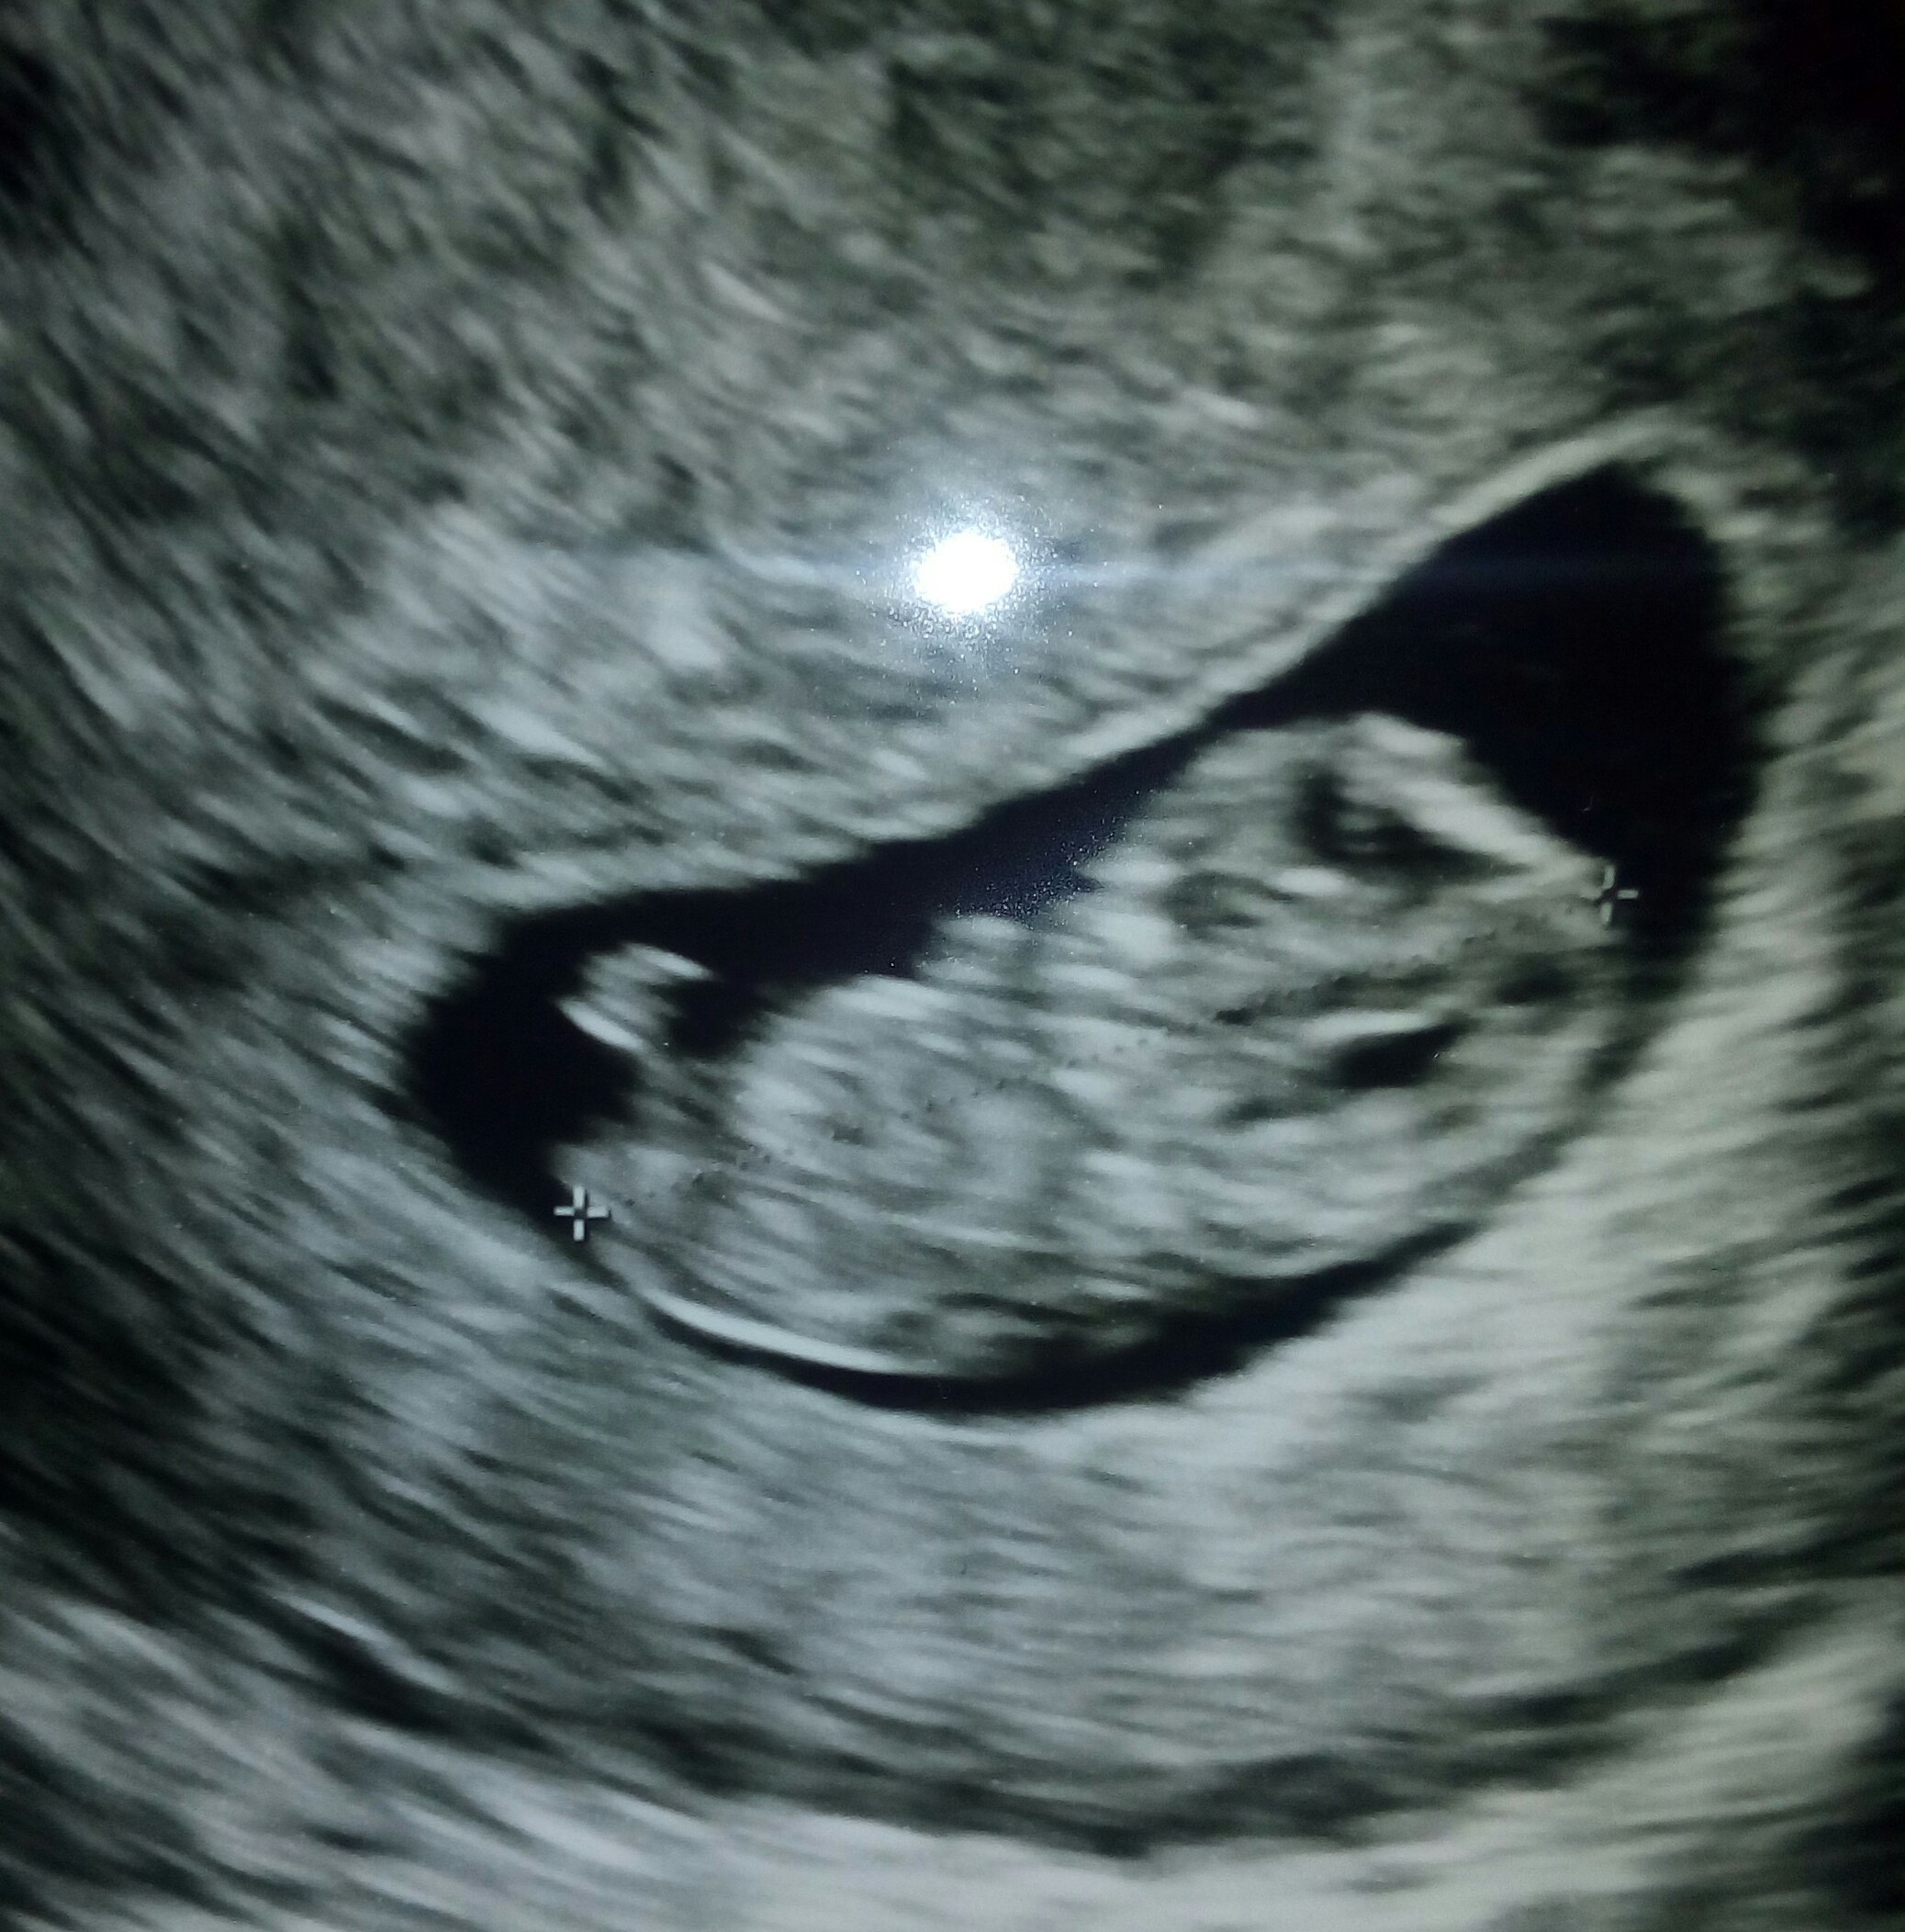

2 wizyta 22 marca [emoji173]